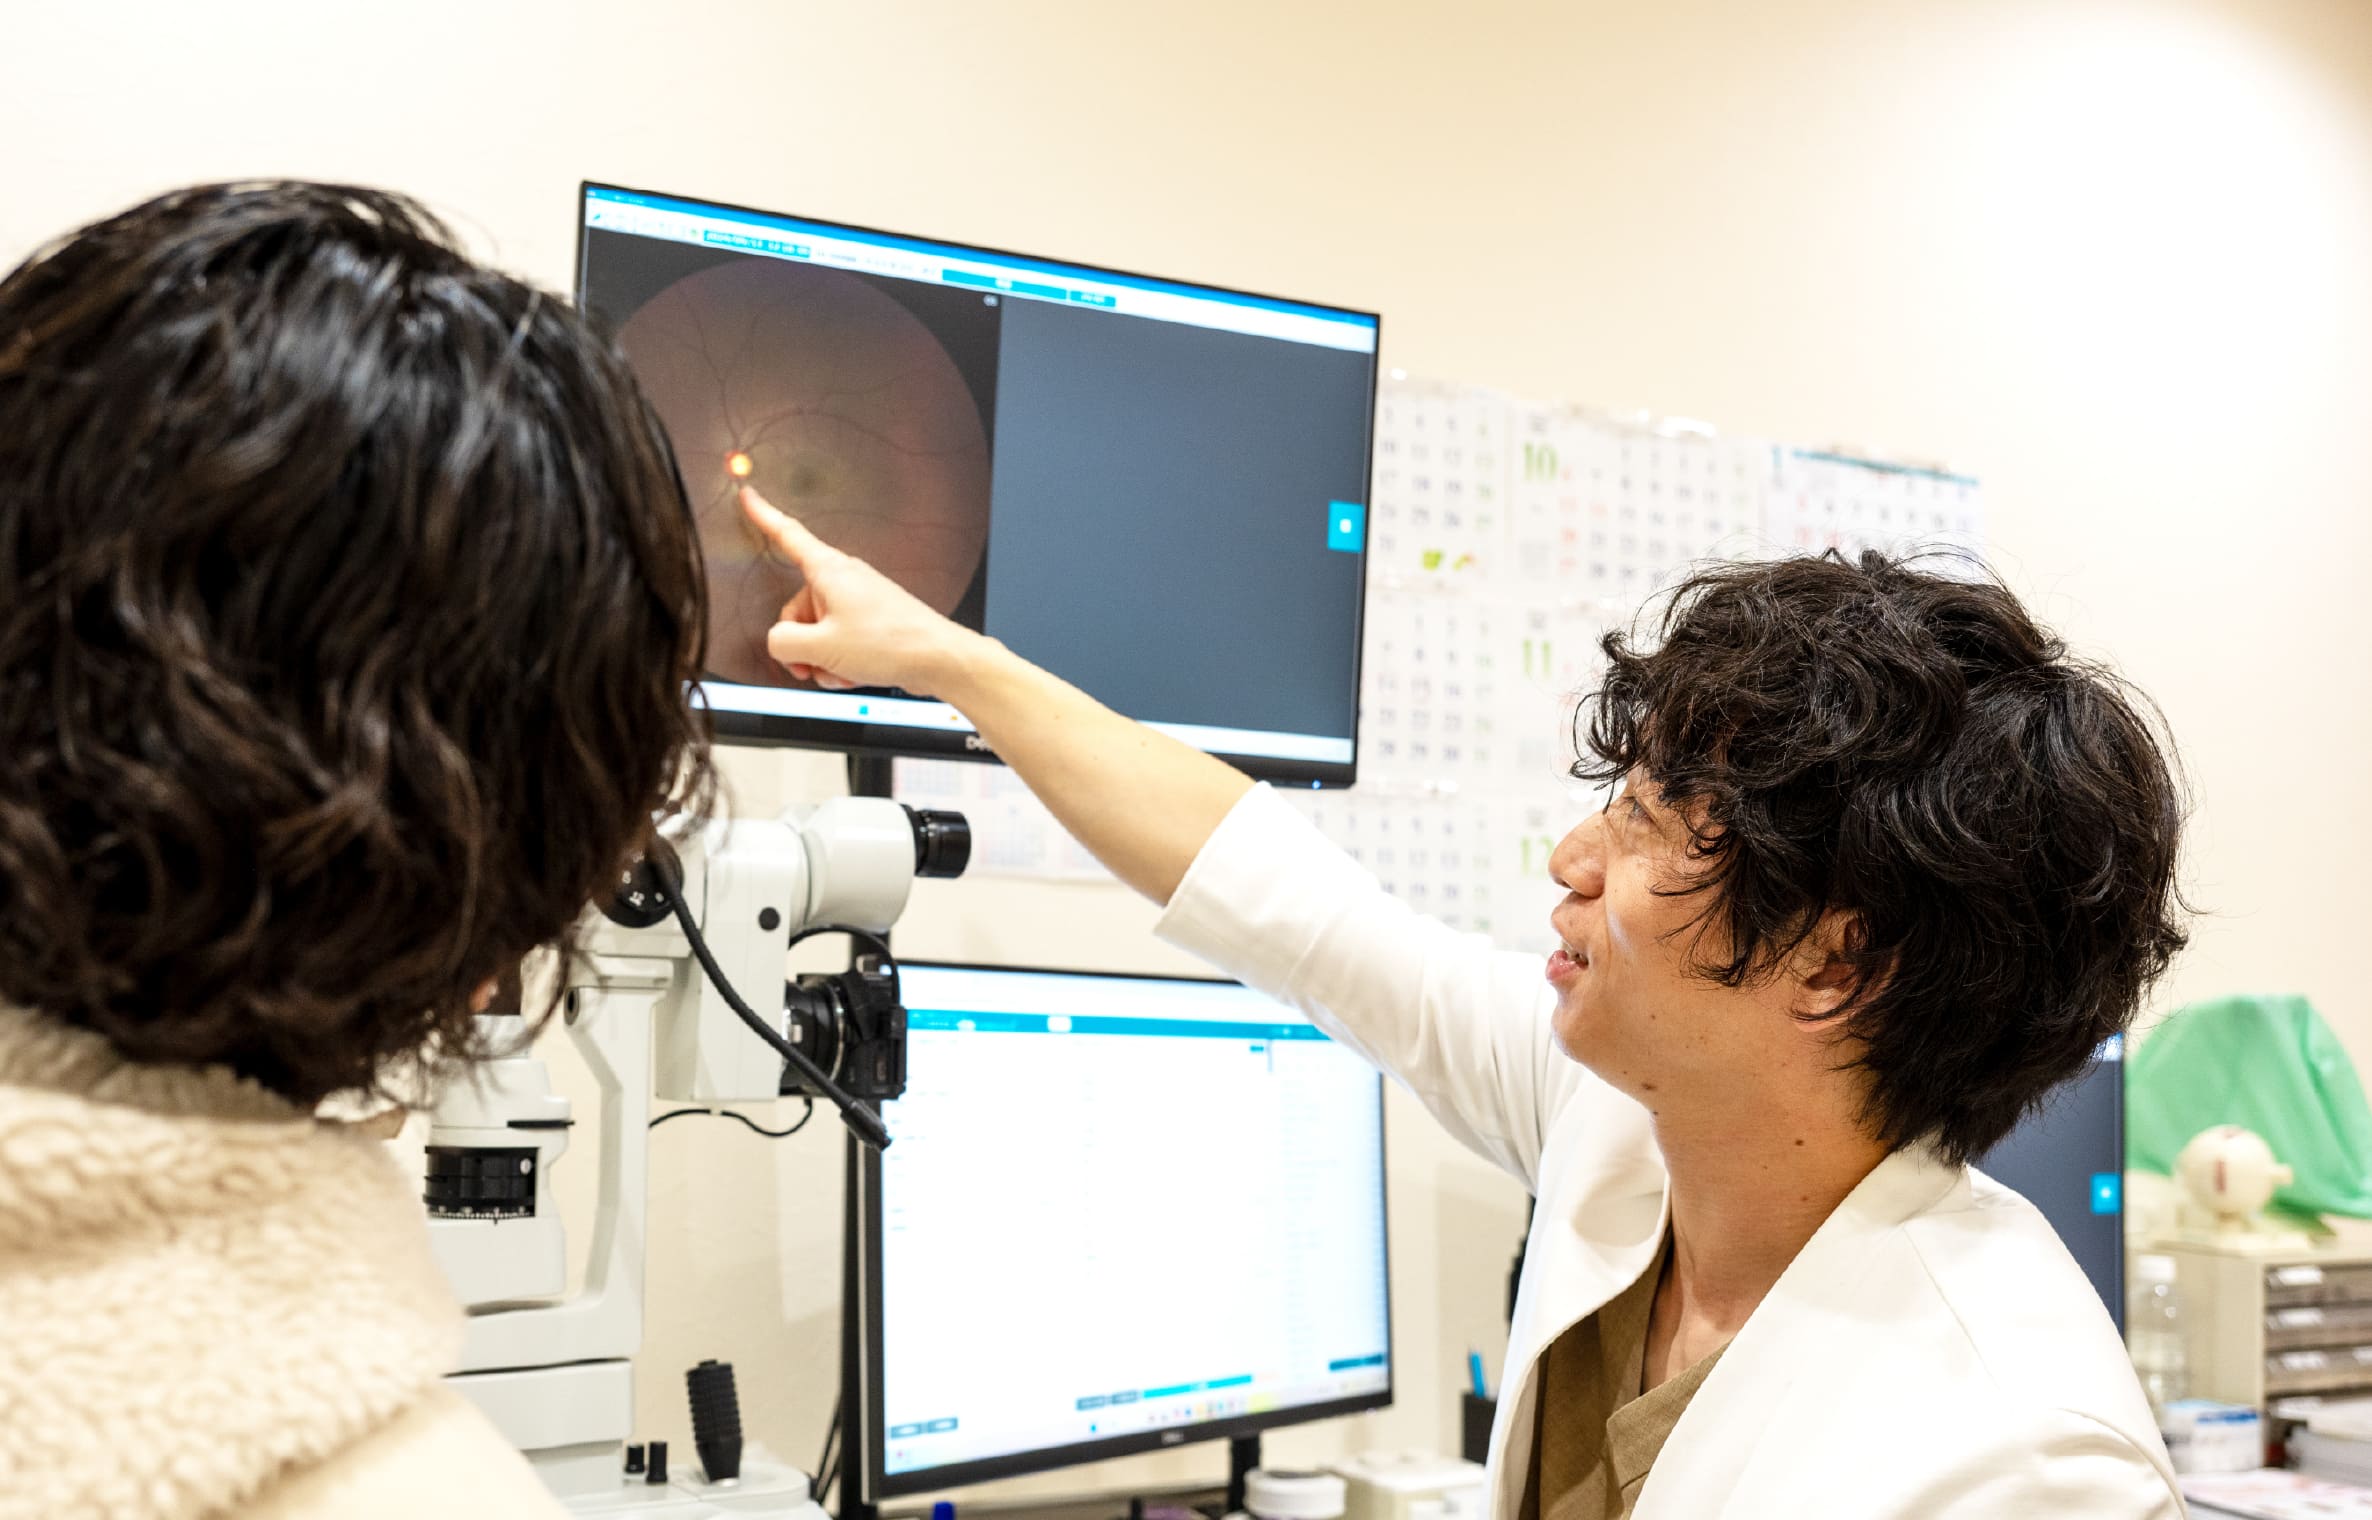

当院では、副院長が診察から手術までを担当。安心して手術を受けていただけます。

1診察・診断

- 細隙灯顕微鏡検査

- 白内障の進行度合いを観察します。